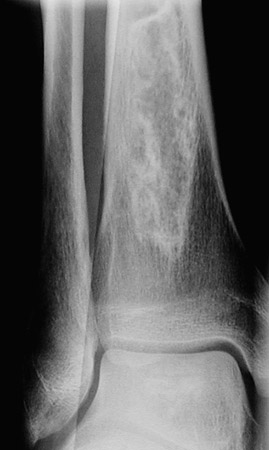

The focal irregular areas of bone remodelling seen above in the calcaneus and below in the distal tibia represent areas of bone infarction. This is an uncommon event, but can occur with sickle cell anemia.